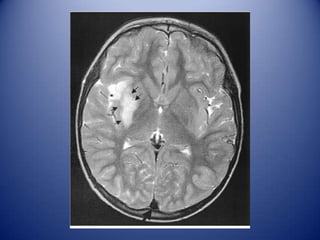

Identifying differential diagnosis

Embolic infarct.

Opportunistic infection.

Brain abscess.

NP SLE.

Brain tumor.

MRI Diagnosis

Radiology: Infarcts (embolus), cortical,

in two different territories, restricted

diffusion, low ADC.

Neurology: Opportunistic infection

(toxoplasmosis) vs. brain abscess